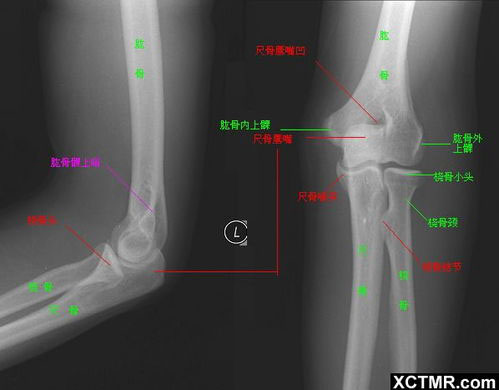

問(wèn):需不需要攝片檢查?

答:不需要,因?yàn)槠由峡床坏饺魏萎惓1憩F(xiàn)。